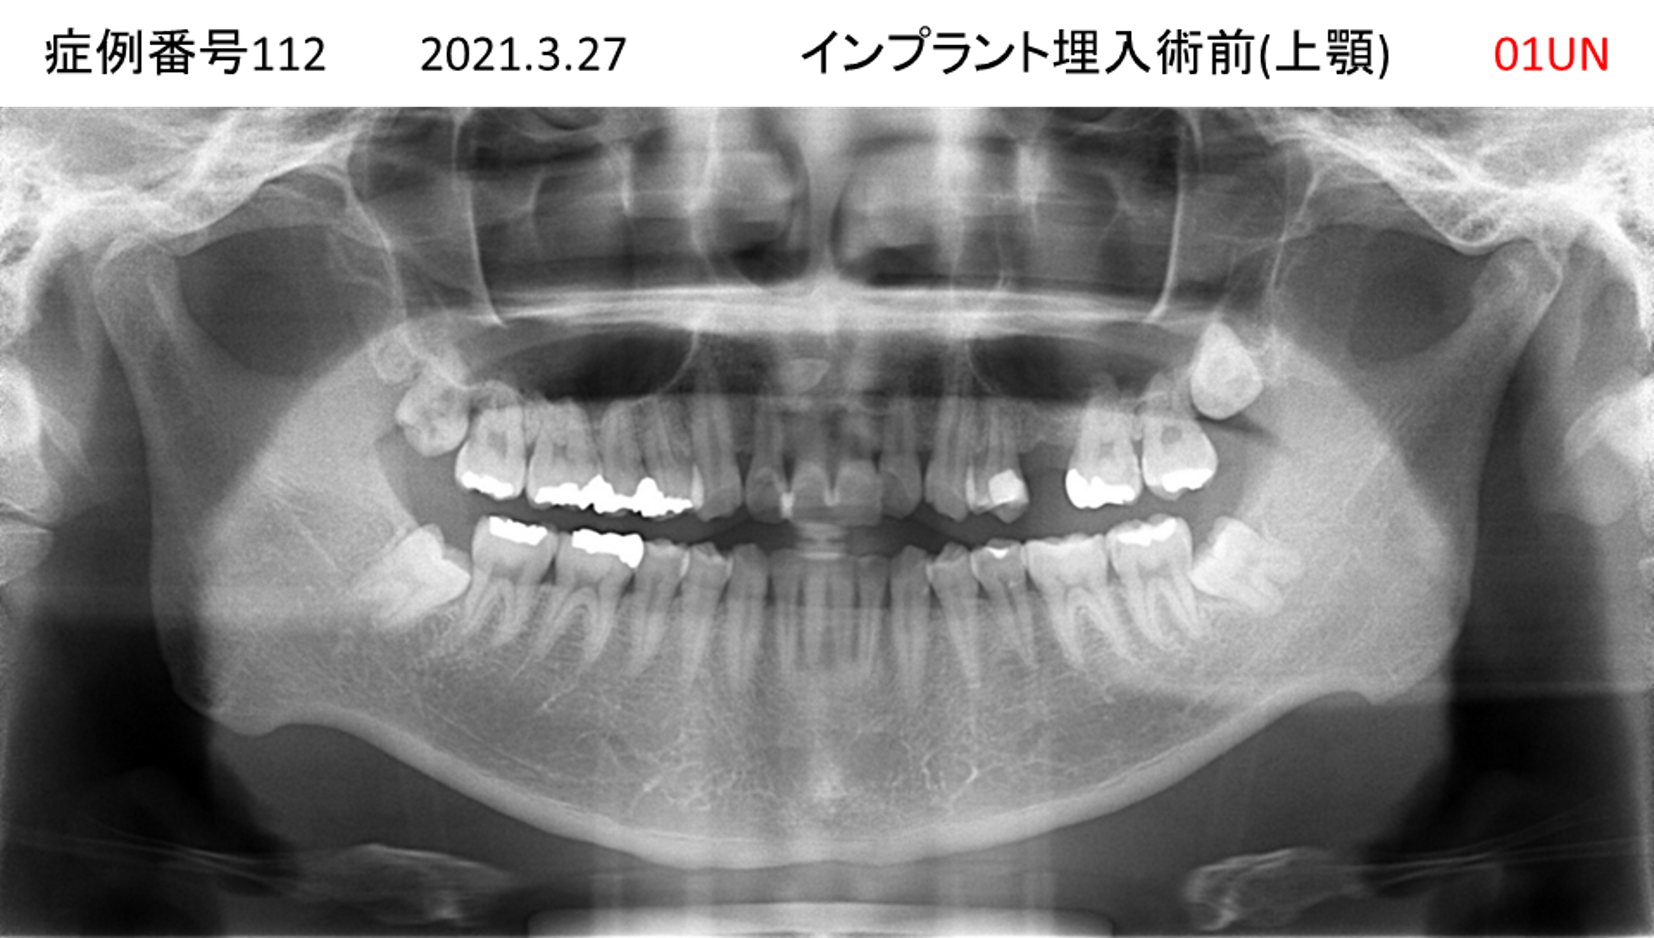

上の前歯が揺れてきてかめない患者様のインプラント症例

| 治療名称 |

インプラント |

| 治療費用 |

335万円+税 |

| 治療期間 |

4か月 |

| 患者さんの症状(主訴) |

上の前歯が揺れてきて噛めない |

| 治療内容 |

サイナスリフト 抜歯即時インプラント |

| 治療結果 |

ちゃんと噛めるようになった。不安がなくなった。見た目がとても良くなったのすごくうれしい。 |

| 治療の注意点(リスク/副作用) |

インプラントが壊れたら再治療が必要 |